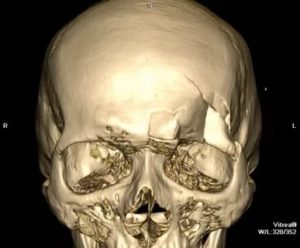

КТ перелома фронтального синуса

Диагностика проводится по клинической картине, результатам КТ.